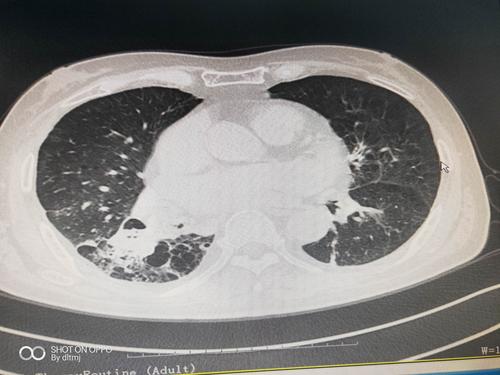

支气管扩张痰液分层

支气管扩张痰液分层,支气管扩张杵状指

支气管扩张,自发性气胸,肺复张术后,痰液潴留,经支气管镜吸痰处理后

支气管扩张关键要把痰咳出来,淤在里面会反复感染.

支气管扩张的ct图片

支气管扩张痰液分层图

支气管扩张的痰液图

支气管扩张图片

支气管扩张图片样子